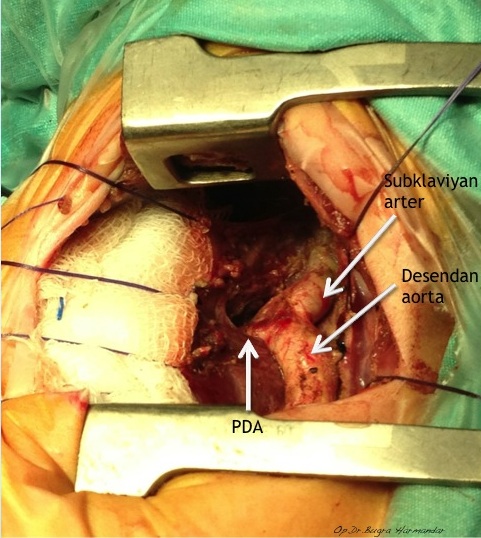

Arkus aorta hipoplazisi + aort koarktasyonlu uygun vakalarda arkus aorta rekonstrüksiyonunu off-pump (kardiyopulmoner bypass kullanılmaksızın) gerçekleştiriyoruz. Kardiyopulmoner bypass kullanılmaksızın gerçekleştirilen bu işlem sayesinde hem ameliyat riski hem de hastaların yoğun bakımda kalış süreleri ciddi oranda azalıyor.

Repair of aortic coarctation is usually performed via a left thoracotomy without cardiopulmonary bypass. There are a number of techniques available to repair the coarctation, each with its own advantages and disadvantages.